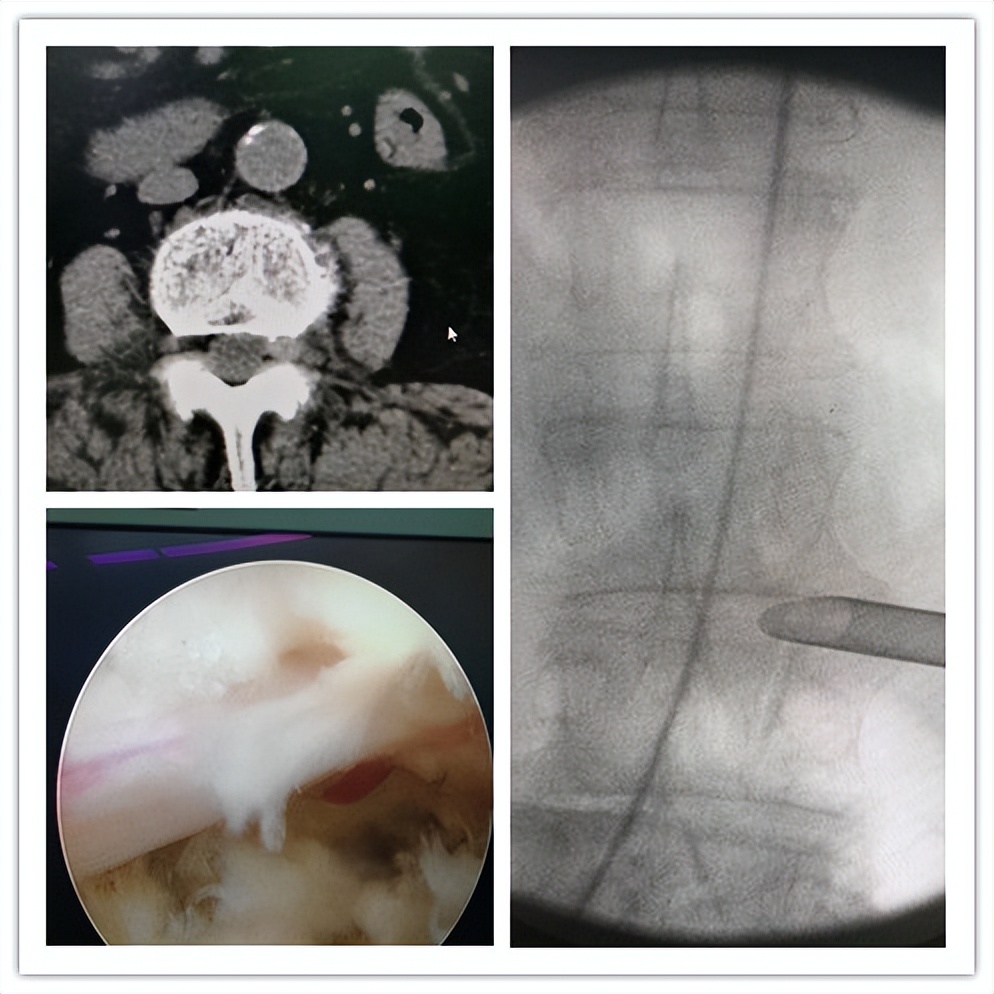

(腰椎间盘突出症:椎间孔镜下腰椎间盘髓核摘除)